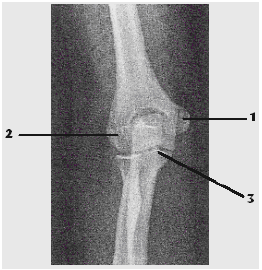

Observe a imagem radiográfica abaixo e assinale a alternativa que apresenta corretamente as estruturas assinaladas.